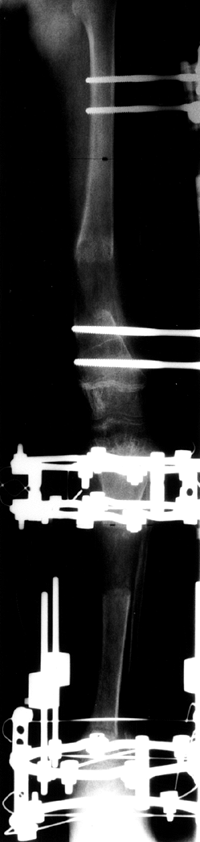

rate of growth either by direct injury to the cells responsible for

growth or by formation of a bony bridge that tethers the epiphysis to

the metaphysis. Salter and Harris provided a classification of

fractures of the physeal plate that is useful in anticipating the

effect of fractures on future growth (49). This classification is shown diagrammatically in Figure 29.14.

Fractures can wander through all zones of the plate, but tend to pass

through the zone of cell hypertrophy where the material is weakest and

the amount of material is least. The material in that zone is

cartilage, which is weaker than bone, and because the cells there are

large, the ratio of matrix volume to cell volume is low (Fig. 29.15).